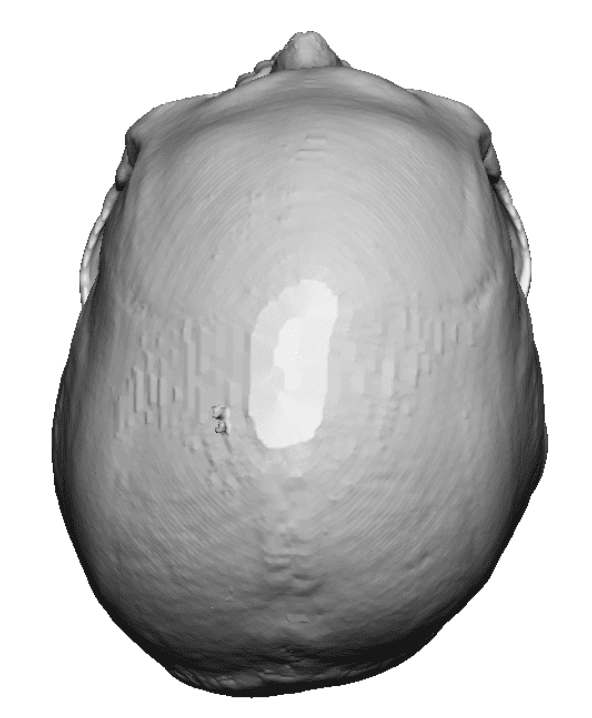

Desire for a higher and more prominent crown of the skull.

Crown of skull augmentation using a custom skull implant.

Desire for a higher and more prominent crown of the skull.

Crown of skull augmentation using a custom skull implant.